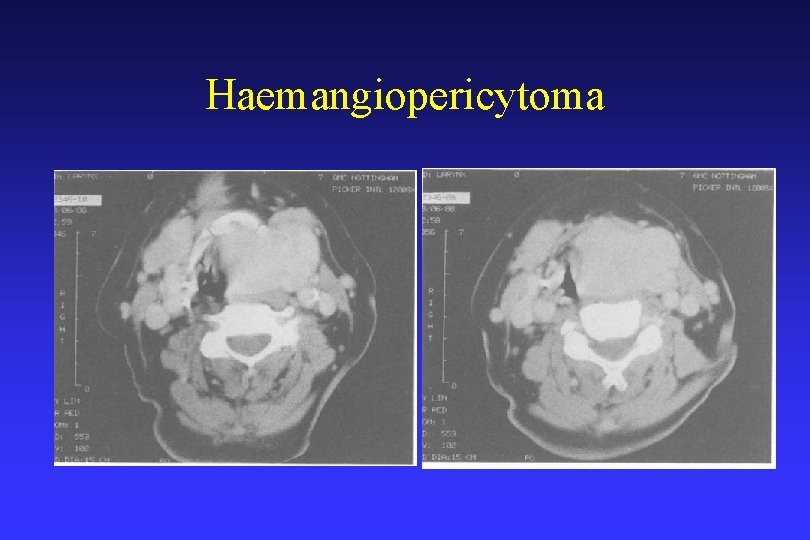

Haemangiopericytoma

Haemangiopericytoma • Hemangiopericytoma (HPC) is a vascular tumor • Originates in the pericytes of the vessels and can therefore occur in any capillary tissue. • May occur at any site, more frequently involving the lower limbs, the pelvis and the retroperitoneum; • Origin being the head and neck is uncommon. • Surgical ablation of HPC seemed to be the only satisfactory method of treatment.